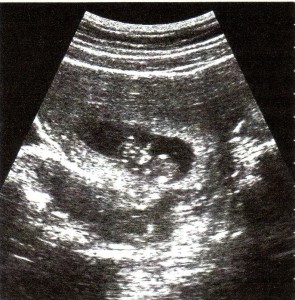

“lho…lho…ini Ibu hamil…” masih kuingat jelas ucapan dokter Adi sekitar 3 minggu lalu yang mengejutkan aku dan suamiku. “Hamil dok?!..kok bisa ya?..” sahutku spontan yang kemudian kusadari sebagai ucapan yang konyol. :hmm: Dokter kemudian menunjukkan di layar monitor janin kami yang hari itu berusia 7 minggu. Dengan takjub kami melihat setitik gambar yang berdenyut-denyut di layar monitor. Kata dokter jantungnya sudah terbentuk, berdenyut dan secara keseluruhan perkembangan janin kami baik dan sehat. Kami berdua berpandangan dan tersenyum, walaupun tidak direncanakan dan mengejutkan, mengetahui bahwa aku hamil memberi perasaan bahagia…kami akan memiliki bayi… :gembira: